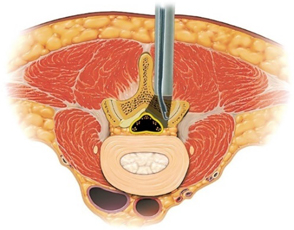

上図のように、FESS法には2つの経路があります。側方経路が椎間孔アプローチ、後方経路が経椎弓アプローチといわれています。手術術式はそれぞれのケースで異なっています。

上図は椎間孔アプローチです(左図)。内視鏡を椎間板に平行にして椎間板ヘルニアに近づけます(中央図)。椎間板ヘルニアを摘出しています(右図)。